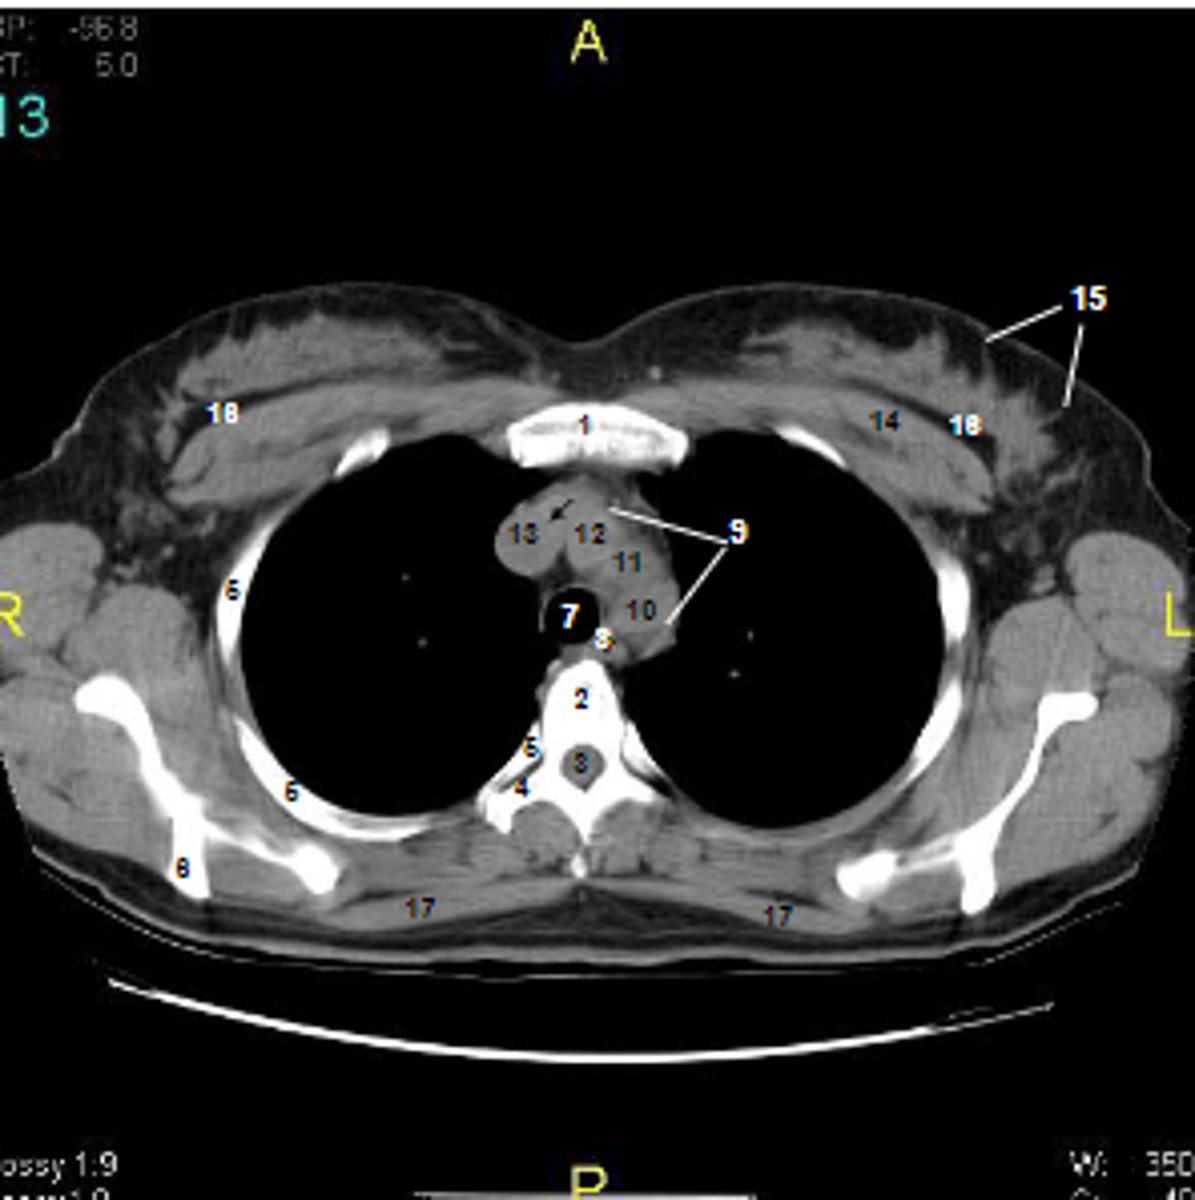

1

at what number is the sternum

2

at what number is the vertebral body

3

at what number is the vertebral canal/ spinal cord

4

at what number is the transverse process of vertebra

5

at what number is the rib

6

at what number is the spine of scapula

7

at what number is the trachea

8

at what number is the esophagus

9

at what number is the arch of aorta

10

at what number is the left subclavian artery

11

at what number is the common carotid artery

12

at what number is the brachiocephalic trunk

13

at what number is the superior vena cava

14

at what number is pectoralis major

15

at what number are Cooper's ligaments

16

at what number is the retromammary space

17

at what number is trapezius